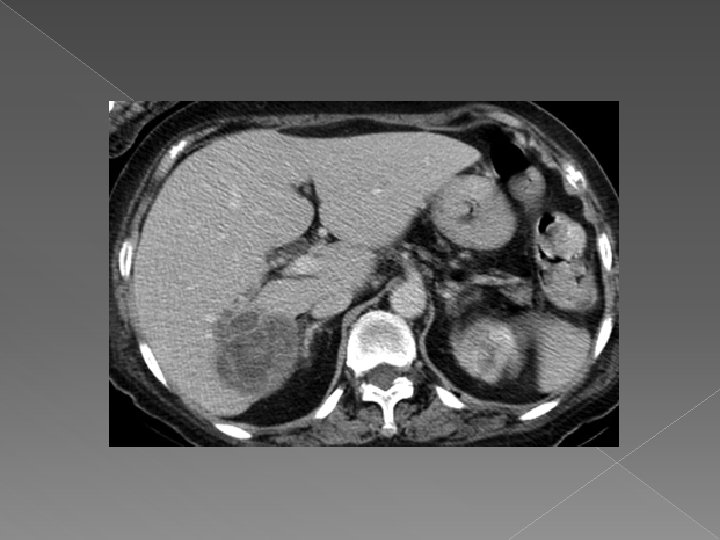

Computer tomografia Tehnica: -sectiuni contigui de 8 -10 mm, 5 mm pentru hil si cai biliare -nativ +contrast: cu rol in diferentierea leziunilor de parenchimul normal q Leziunile focale • Sunt de regula spontan hipodense • Incarcare mai mica decat a parenchimului hepatic Exemple: v Tumori hepatice-primitive sau secundare v Chiste; v Abcese; v Hematoame; v Steatoza.

Abces hepatic